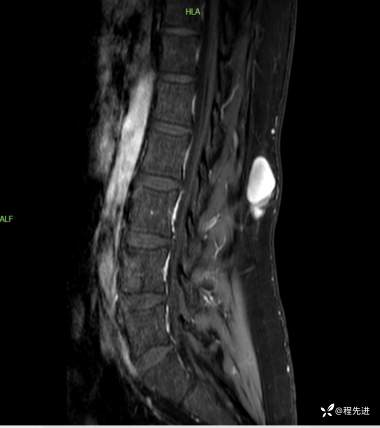

T2压脂矢状位:

T1增强压脂矢状位:

T1增强压脂冠状位: